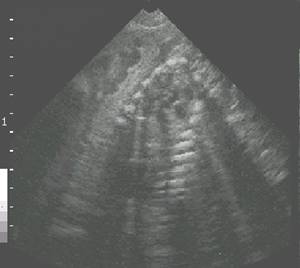

Fetal skeleton